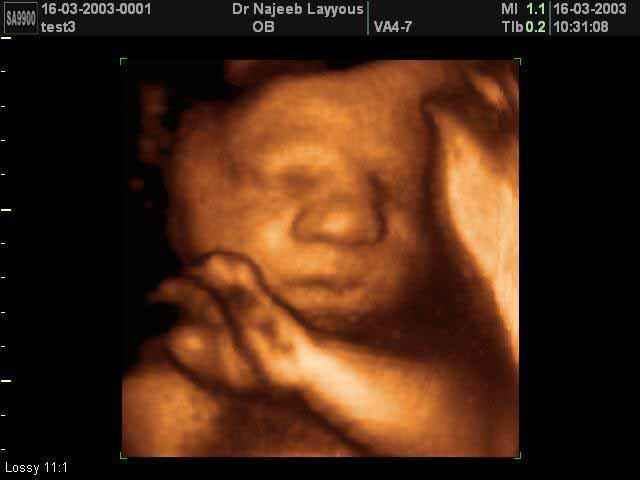

- Fetal Face Ultrasound Photos

- Fetal Behavior Ultrasound Photos

3D Fetal Face Ultrasound Scan Photos | Dr N Layyous